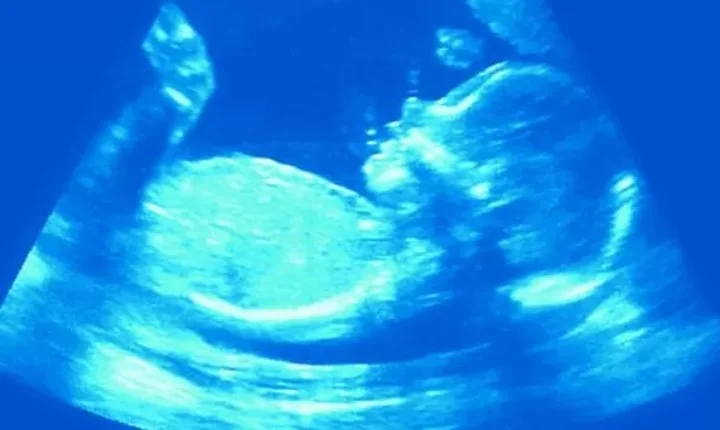

வயிற்றில் இருக்கும் கருவுக்கும் விக்கல் வருவது அல்ட்ராசவுண்ட் ஸ்கேன் மூலமாக சில நேரங்களில் தெரியவந்துள்ளது. குழந்தை பிறக்கும் போது, நுரையீரலுக்குள் மூச்சுக்காற்றை உள்ளே இழுப்பதற்கு தயாராகும் வகையில் குழந்தைகளுக்கு விக்கல் ஏற்படுவதாக சில ஆய்வாளர்கள் நம்புகின்றனர்.